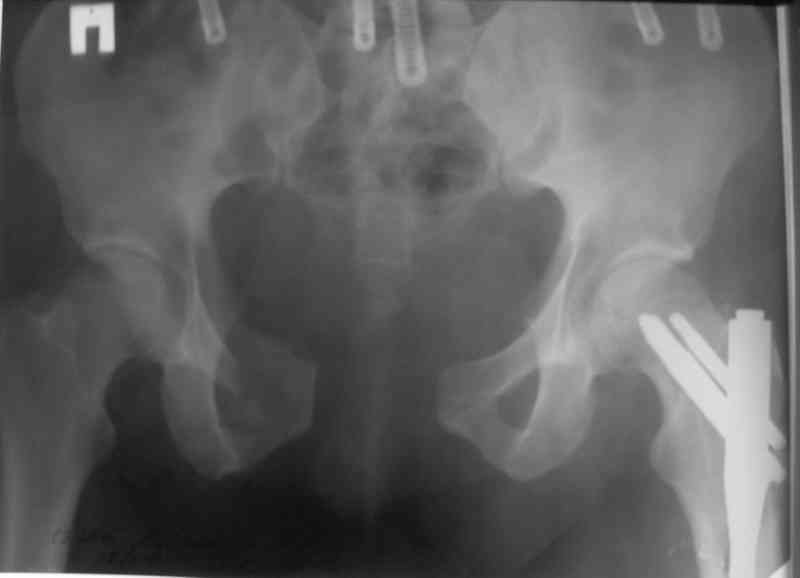

> метод фиксации таза: стержневой аппарат (тазового набора Илизарова нет в округе)

> каннюлированными винтами,

> передняя фиксация пластиной правого крестцово- подвздошного сочленения

Пластина спереди (на лонные кости) открыто и каннюлированные винты с обеих сторон сзади - закрыто.

Предварительная репозиция может быть достигнута при помощи аппарата.